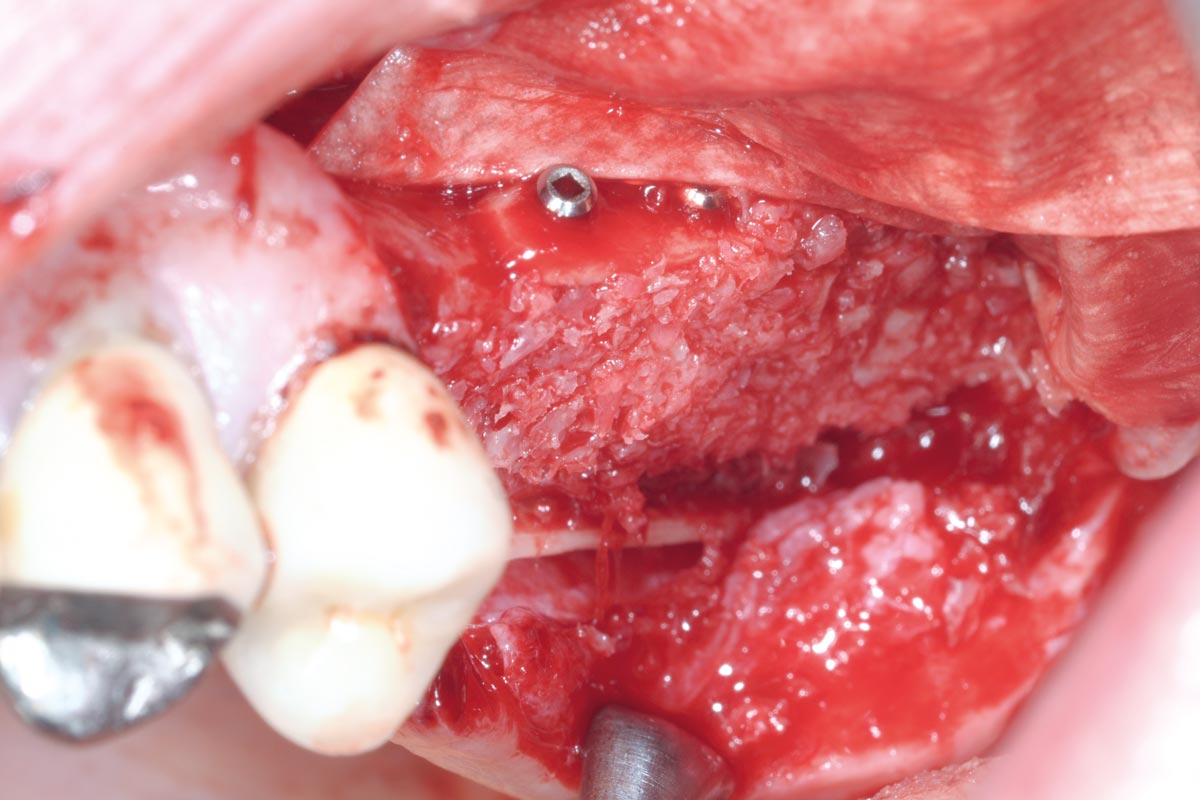

5/15 - Filling of the container with maxgraft® cortico-cancellous granulesTreatment of a combined horizontal and vertical bone defect in the maxilla with maxgraft® cortico in the allogenic shell technique - Dr. R. Würdinger